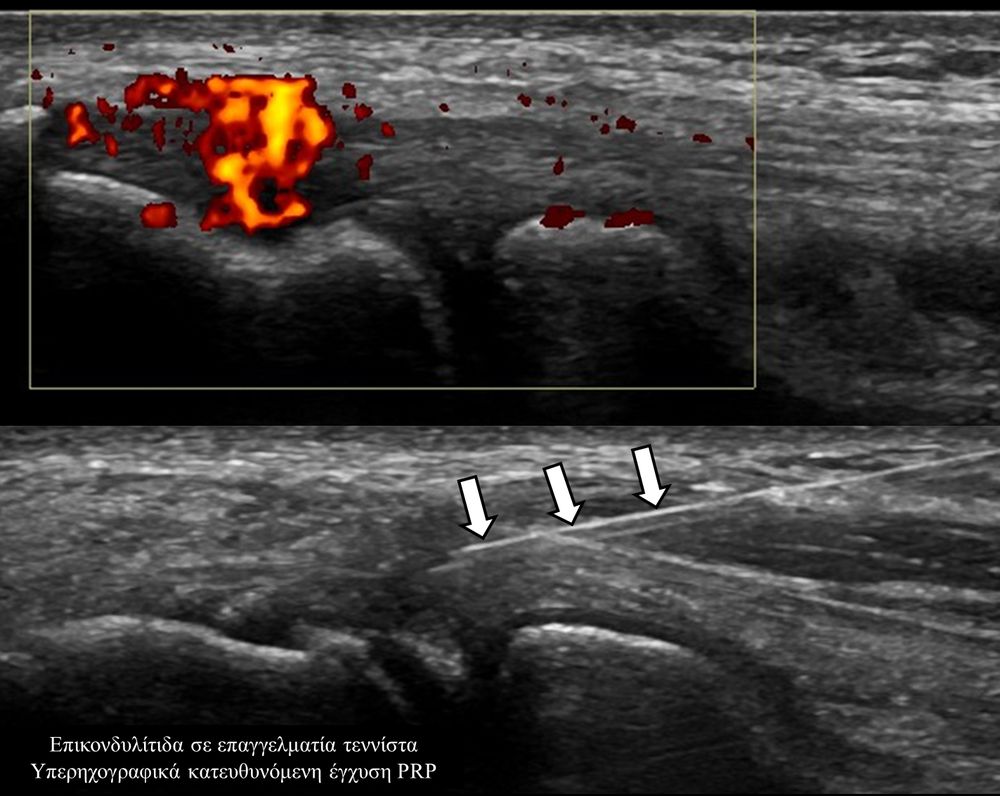

Οι κατευθυνόμενες εγχύσεις σε αθλητικές κακώσειςαποσκοπούν στη μείωση του πόνου, την ενίσχυση της αποτελεσματικότητας της φυσικοθεραπείας και την επιτάχυνση της διαδικασίας επούλωσης για την πιο γρήγορη επάνοδο του αθλητή στις αθλητικές του δραστηριότητες. Η πιο διαδεδομένη έγχυση αποτελεί η έγχυση PRP.Ανήκει σε μια σύγχρονη θεραπευτική μέθοδο γνωστή ως Ορθοβιολογική θεραπεία και βασίζεται την ικανότητα του οργανισμού να θεραπεύεται με τα δικά του αποκλειστικά θεραπευτικά μέσα χωρίς να υπάρξει χρήση φαρμάκων.Το PRP (Platelet Rich Plasma)-πλάσμα πλούσιο σε αιμοπετάλια- σήμερα αποτελεί μια θεραπευτική μέθοδο πρώτης γραμμής με σχετικά μεγάλη επιτυχία για την επούλωση τραυματισμένων τενόντων, μυών και εκφυλιστικών παθησεων όπως οστεοαρθρίτιδα.Η εφαρμογή του περιλαμβάνει μία ευρεία ποικιλία από παθήσεις όπως:

- Επικονδυλίτιδα αγκώνα

Η έγχυση γίνεται πάντοτε με την βοήθεια υπερηχογραφικού ελέγχου ώστε να είμαστε απόλυτα σίγουροι για το σημείο έγχυσης τοπικά.